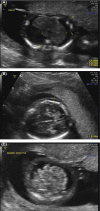

Novel mutation in CCBE 1 as a cause of recurrent hydrops fetalis from Hennekam lymphangiectasia-lymphedema syndrome-1

Whole exome sequencing (WES) was used to determine the etiology of recurrent hydrops fetalis in this case of Hennekam lymphangiectasia-lymphedema syndrome-1. WES is a useful approach for diagnosing rare single-gene conditions with nonspecific phenotypes and should be considered early in the diagnostic process of investigating fetal abnormalities.